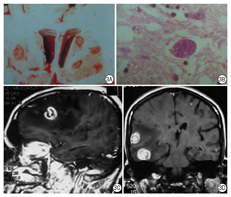

病理改变:弓形虫脑炎的病理特征为形成多发脓肿性疾病,最常累及大脑皮髓质交界处和大脑基底核部位,也可累及脑干、小脑,偶尔累及脊髓。主要是脑组织多灶性坏死,病灶中心神经细胞变性坏死消失,周围血管充血,伴淋巴细胞浸润和小胶质细胞增生,边缘部位较易查见弓形虫假囊和游离速殖子(滋养体)(图3A、图3B)。

影像表现:MR T1WI上病变为低强度信号,T2WI病灶为中等强度信号,周围水肿带为高强度信号,静脉内注射对比剂(Gd-DTPA)后,病灶本身呈高信号,而水肿带不增强(图3C、图3D)。影像检查也用于弓形虫的疗效评估等[5]。